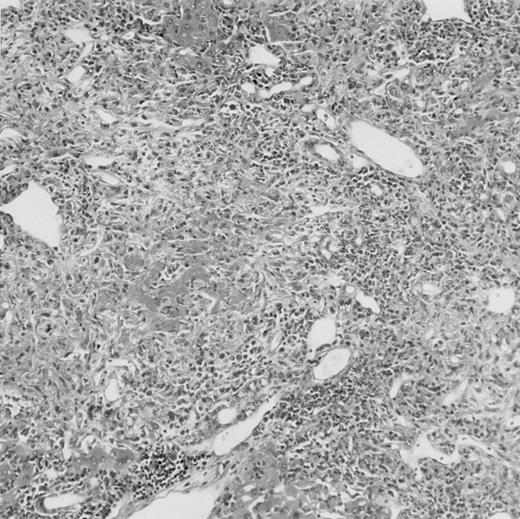

Histologic findings. Organs were collected at different times after BMT and tissue sections were stained with hematoxylin and eosin. Original magnifications for spleen (left) and liver (right) are ×40 and ×100, respectively. (A) B6 mice receiving FVB BM plus EpTK T cells. (B) Control group receiving BM only.

(C) B6 mice receiving FVB BM plus EpΔTK T cells and treated with GCV. (D) B6 mice receiving FVB BM plus EpΔTK T cells, treated with GCV, and developing a late onset GVHD (day 54).

Protection from GVHD was slightly less efficient in the group receiving EpΔTK CD3+ T cells. The survival rate was 79% at day 60 and 67% at day 120 (Fig 2B). However, two different outcomes must be distinguished. On the one hand, a majority of mice behaved as GCV-treated animals receiving EpTK T cells. They were apparently healthy, presented no skin lesions during a 120-day observation period, and showed complete donor-type hematologic reconstitution. There were no histological signs of GVHD in the spleen or liver (Fig 4C).

On the other hand, 5 of 19 mice exhibited signs suggesting the occurrence of a delayed GVHD (Table 1). Clinically, these animals presented weight loss and/or skin lesions on ears, neck, limbs, or abdomen, but only after day 40. In the absence of any further GCV treatment, 2 mice died 14 and 29 days after the occurrence of these signs (Table 1A) with histological signs of severe GVHD (Fig 4D). These results suggest that, in these mice, the 7-day GCV treatment was sufficient to prevent early, but not delayed GVHD.